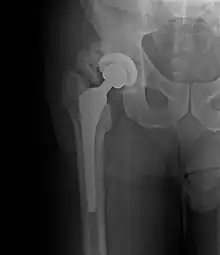

Heterotopic ossification around the hip joint in a patient who has undergone hip arthroplasty

Heterotopic ossification of varying severity can be caused by surgery or trauma to the hips and legs. About every third patient who has total hip arthroplasty (joint replacement) or a severe fracture of the long bones of the lower leg will develop heterotopic ossification, but is uncommonly symptomatic. Between 50% and 90% of patients who developed heterotopic ossification following a previous hip arthroplasty will develop additional heterotopic ossification.